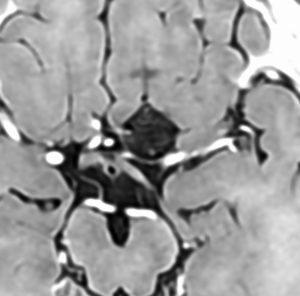

前頭蓋底類皮のう胞

蝶形骨平面から鞍結節上に発生するもので多いタイプです。左側のT2強調画像で内容物がまだらに見え,右側の拡散強調画像で高信号(白い)に見えるので診断確定です。内頸動脈や前大脳動脈や穿通枝などとの癒着が強いものが多いので剥離は難しく要注意です。ある程度の大きさを超えると経鼻内視鏡手術では摘出できません。この腫瘍は脳槽内にあるので,一回の手術でのう胞の壁も含めて全部摘出しなければなりません。そうしないと,手術後に内容物(皮脂と汗とケラチン)が髄液の中に産生されて漏れ出て,難治性の水頭症になります。